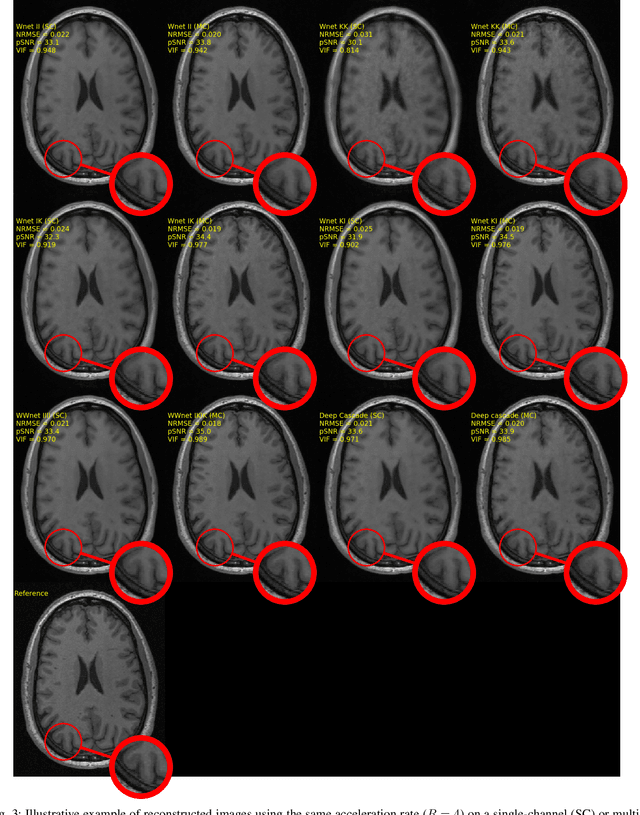

Abstract:The U-net is a deep-learning network model that has been used to solve a number of inverse problems. In this work, the concatenation of two-element U-nets, termed the W-net, operating in k-space (K) and image (I) domains, were evaluated for multi-channel magnetic resonance (MR) image reconstruction. The two element network combinations were evaluated for the four possible image-k-space domain configurations: a) W-net II, b) W-net KK, c) W-net IK, and d) W-net KI were evaluated. Selected promising four element networks (WW-nets) were also examined. Two configurations of each network were compared: 1) Each coil channel processed independently, and 2) all channels processed simultaneously. One hundred and eleven volumetric, T1-weighted, 12-channel coil k-space datasets were used in the experiments. Normalized root mean squared error, peak signal to noise ratio, visual information fidelity and visual inspection were used to assess the reconstructed images against the fully sampled reference images. Our results indicated that networks that operate solely in the image domain are better suited when processing individual channels of multi-channel data independently. Dual domain methods are more advantageous when simultaneously reconstructing all channels of multi-channel data. Also, the appropriate cascade of U-nets compared favorably (p < 0.01) to the previously published, state-of-the-art Deep Cascade model in in three out of four experiments.